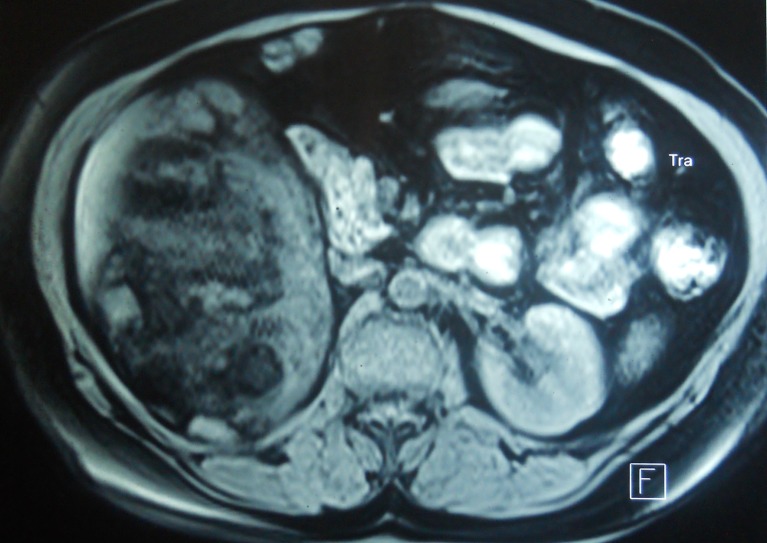

A 43 year old normotensive female presented with complaints of dragging sensation and dull aching pain in the right lumbar region for the past 5 years relieved with oral analgesics. The patient had a known history of allergy to iodinated contrast agents. No other significant history could be elicited. On physical examination, a well defined firm lump could be palpated in the right flank separate from the liver. An ultrasound of the abdomen, revealed an echogenic mass in the upper pole of right kidney with irregular borders, suggestive of a possible renal mass. Routine blood investigations and urine examination were within normal limits for her age and non specific. An MRI of the abdomen was carried out, which noted a large heterogeneous signal intensity lesion in the right suprarenal region with mature and immature fatty component (Fig. 1). The right kidney was seen to be displaced infero-medially and the right adrenal could not be seen separate from the lesion. A possibility of adrenal myelolipoma was suggested. The patient was planned for exploration. A functional adrenal tumor was ruled out by carrying out serum catecholamines and 24 h urinary VMA, which were within normal limits.

Fig. 1.

Large heterogeneous signal intensity lesion in the right suprarenal region with mature and immature fatty component